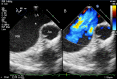

This review article will guide the reader through the basics of echocardiographic assessment of congenital left to right shunts in both paediatric and adult age groups. After reading this article, the reader will understand the pathology and clinical presentation of atrial septal defects (ASDs), ventricular septal defects (VSDs), atrioventricular septal defects (AVSDs) and patent arterial duct. Echocardiography is the mainstay in diagnosis and follow-up assessment of patients with congenital heart disease. This article will therefore describe the echocardiographic appearances of each lesion, and point the reader towards specific features to look for echocardiographically.